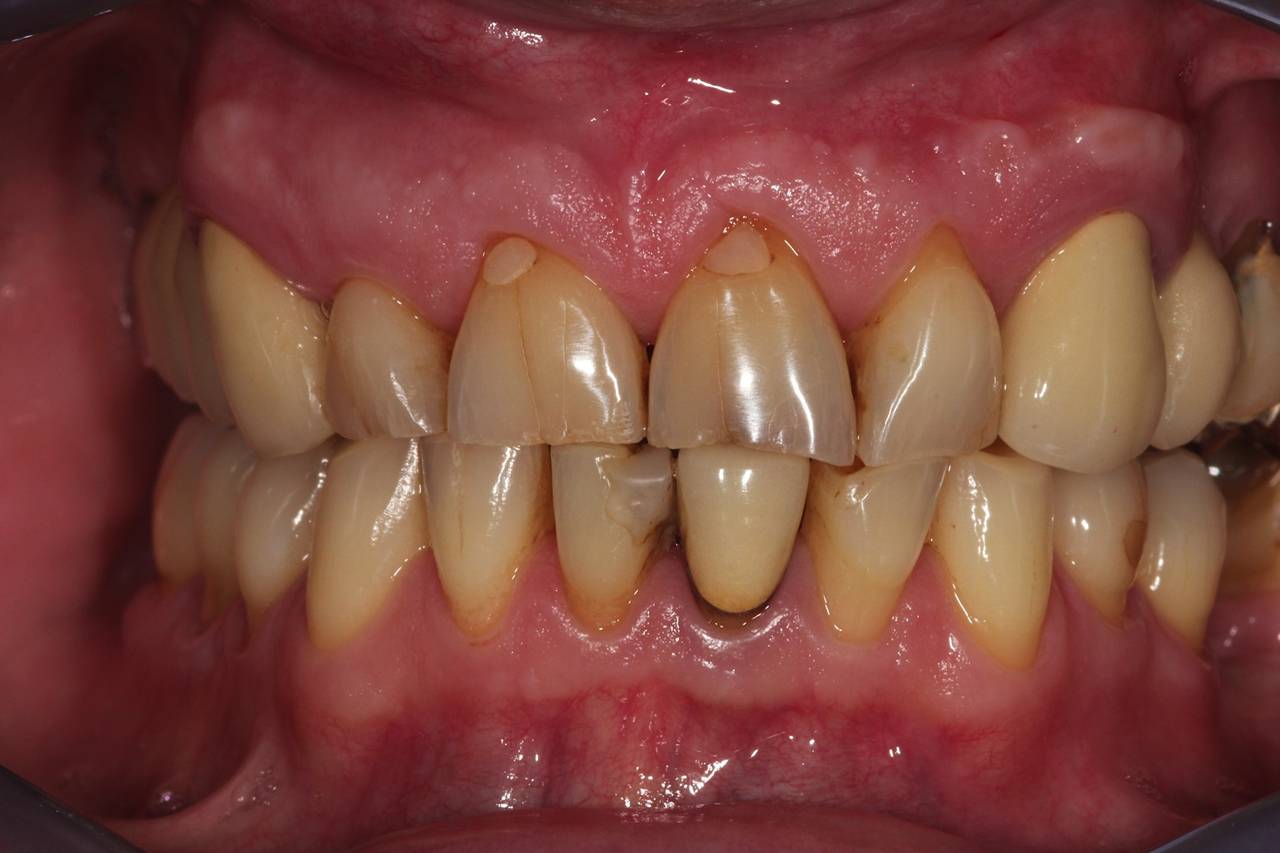

Zirkon -Ausgangssituation